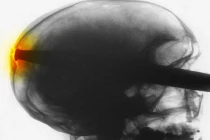

Betty là một con chó bull, thích ăn tất cả mọi thứ, bao gồm cả một mũi tên đồ chơi dài 25cm.